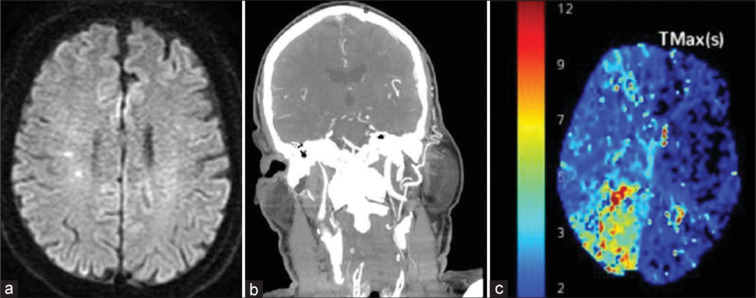

Carotid endarterectomy (CEA) is an established method of stroke prevention in patients with severe carotid artery stenosis, especially in those with symptomatic disease. Complications of CEA include perioperative stroke, cranial nerve palsy, hemorrhage, and vascular dissection. We present an unusual case of a 66-year-old man who presented for elective right CEA for symptomatic 70% right internal carotid artery (ICA) stenosis due to ulcerated plaque. Following surgery, the patient developed fluctuating neurological deficits consistent with involvement of the right middle cerebral artery territory. Imaging revealed possible mild clamp-induced ICA dissection limited to the ICA in the neck. Despite initial successful anticoagulation management in the neurointensive care unit, the patient returned 2 days later with stroke symptoms, necessitating urgent endovascular intervention. Neurovascular interventions involved aspiration thrombectomy and multiple stenting extending distally into intracranial ICA, which successfully restored cerebral arterial perfusion and normal neurological function. This case highlights the first reported instance of extensive intracranial ICA dissection managed with full-length stenting. This article offers an effective endovascular procedure for preventing a devastating stroke from a complication of a procedure that was performed to prevent it.